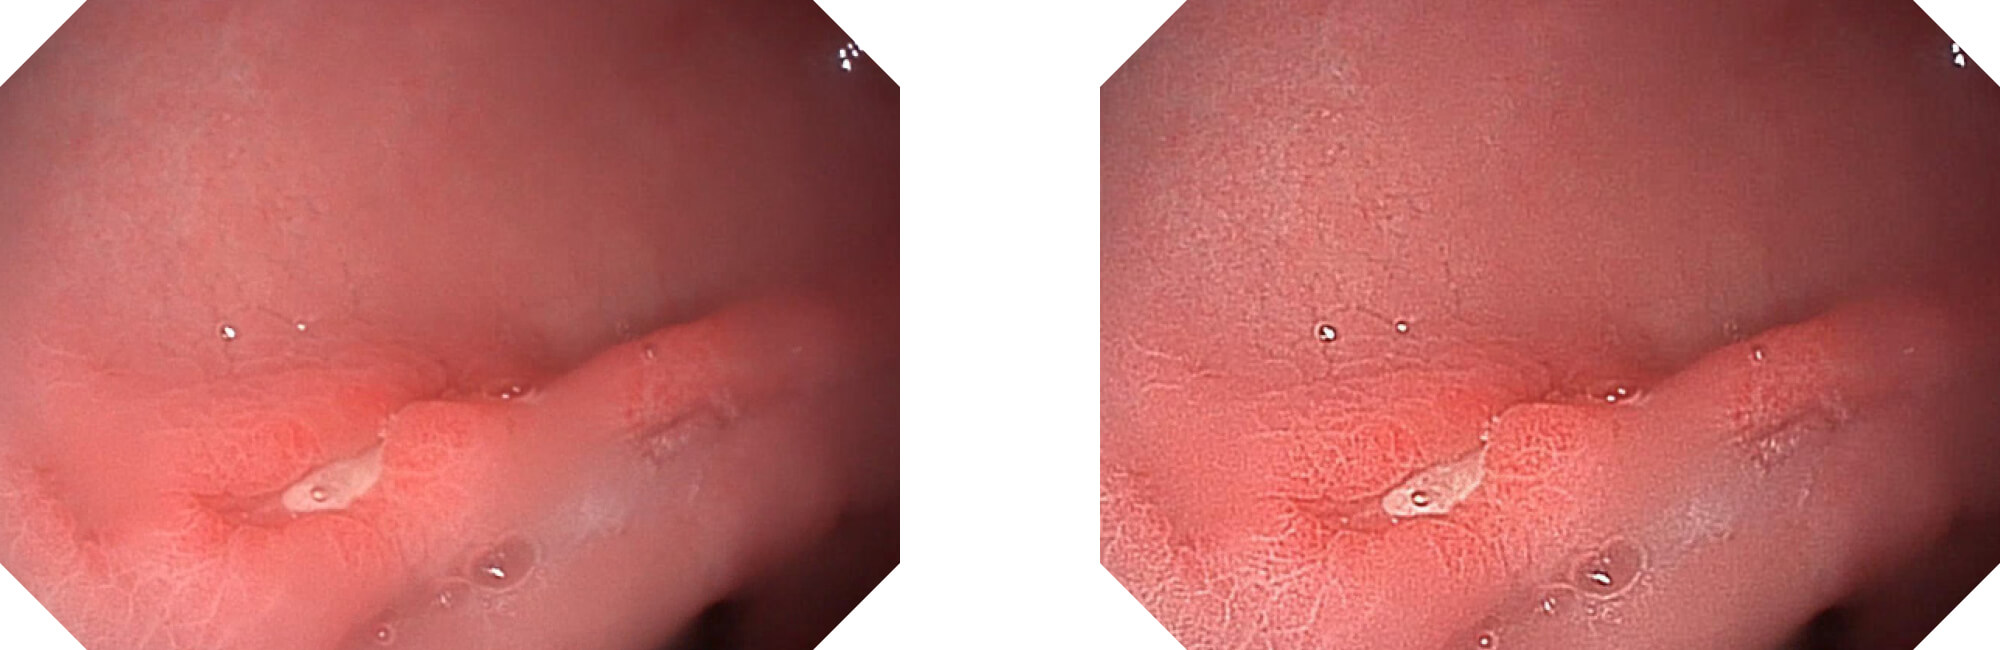

高清数字信号结合构造强调和色彩增强,多重图像处理技术能让每一个图像都清晰可见。

构造强调

色彩增强

利用了血红蛋白在不同波长吸收下系数不同的原理,设计的一种光学域滤波和数字域滤波结合的染色技术,既保证了图像亮度,又可增强黏膜血管的对比度,充分凸显早期病变的细微结构变化,为临床疾病的观察诊断提供更丰富的参考信息。